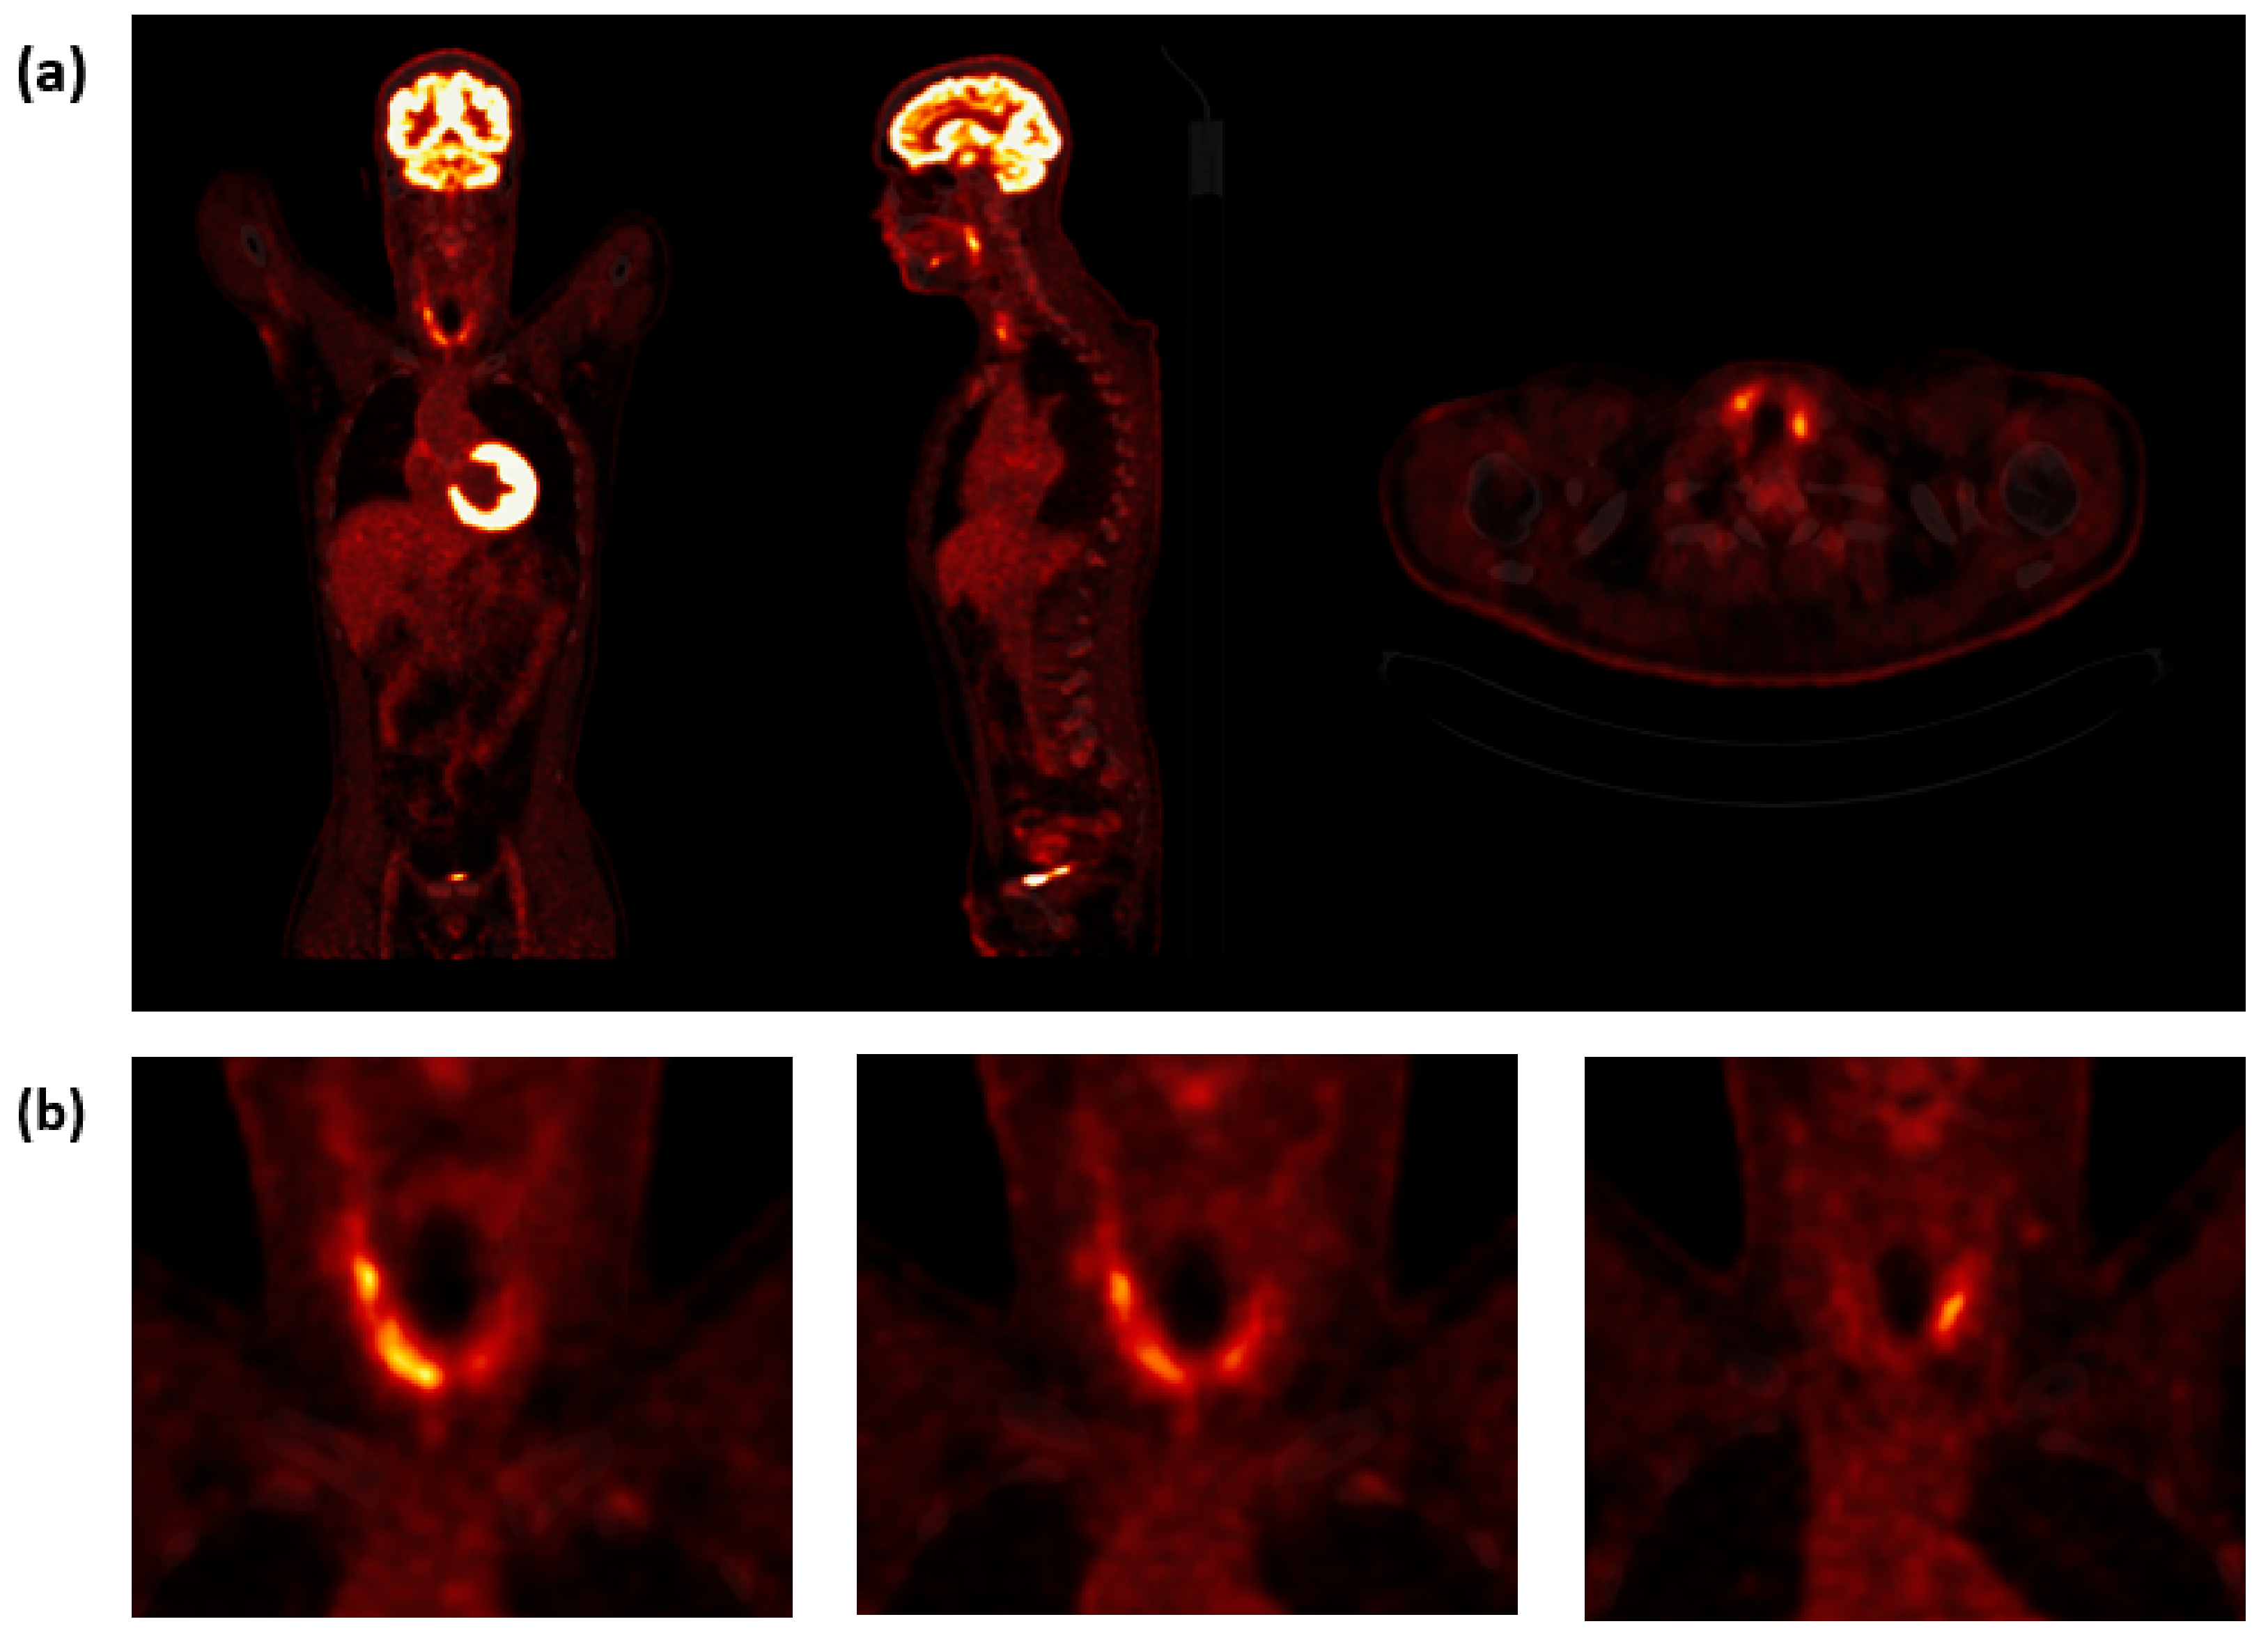

Because of the recurrent FUO and the persistent elevated hsCRP levels, the patient received a full screening for potential viral infections (hepatitis-B-virus surface antigen and antibody, hepatitis-C-virus antibody, HIV-1/2 antigen/antibody, HIV-1/2, PCR acute influenza virus-A and influenza virus-B RNS antigens/antibodies, PCR acute respiratory syncytial viruses RNS as well PCR coronavirus SARS-CoV-2), which was negative. Urine test was negative. Blood cultures were taken and did not show bacterial growth in both aerobic and anaerobic cultures. Echocardiography and chest radiography were also performed. Despite antibiotic treatment, the patient still reported recurrent FUO and persistent elevated levels of hsCRP. Then, 2-[18F]FDG PET/CT at the Department of Nuclear Medicine at Vienna General Hospital was performed to find a possible focus of inflammation or infection. The PET only showed multiple 2-[18F]FDG hotspots in both thyroid lobes, mostly on the right (Figure 1).

Figure 1.

2-[18F]FDG PET/CT imaging. (a) Coronal, sagittal, and transversal 2-[18F]FDG PET/CT images slices showing high tracer uptake in both lobes of the thyroid. (b) Representative coronal PET/CT images of multiple 2-[18F]FDG-hot spots in both thyroid lobes, mostly on the right. PET/CT, positron emission tomography/computed tomography; 2-[18F]FDG, 2-deoxy-2-[18F]fluoro-d-glucose.

In this case report, we analyzed a case of atypical SAT originally presenting with a clinically history of FUO and elevated levels of hsCRP, without the typical symptom of neck pain. The patient underwent 2-[18F]FDG PET/CT examination, and we observed a diffuse, inhomogeneous 2-[18F]FDG uptake in the thyroid, which led us to examine the thyroid, resulting in a final diagnosis of SAT. Other causes of FUO or IUO were not found.

2-[18F]FDG is an analog of glucose and is taken up by living cells via cell membrane glucose transporters and subsequently phosphorylated with hexokinase inside most cells. 2-[18F]FDG accumulation in tissue is proportional to the amount of glucose utilization, and it can be used to obtain quantitative parameters concerning the metabolic activity of target tissues [1,4]. It is known that 2-[18F]FDG PET is a well-established method in oncological imaging. However, it also has an important role in identifying infection and areas of inflammation [4]. To our knowledge, there have only been a few published cases of patients suffering from SAT who underwent 2-[18F]FDG PET imaging [7,8,9]. In two of these cases, the patient demonstrated thyrotoxicosis [7,8], and in one case report, the patient had normal thyroid function [9]. 2-[18F]FDG PET imaging showed in all three cases an asymmetrical increased tracer uptake in the thyroid [7,8,9]. Our patient presented with diffuse, inhomogeneous 2-[18F]FDG avidity in the entire thyroid, which is consistent with the previous reports [7,8,9].